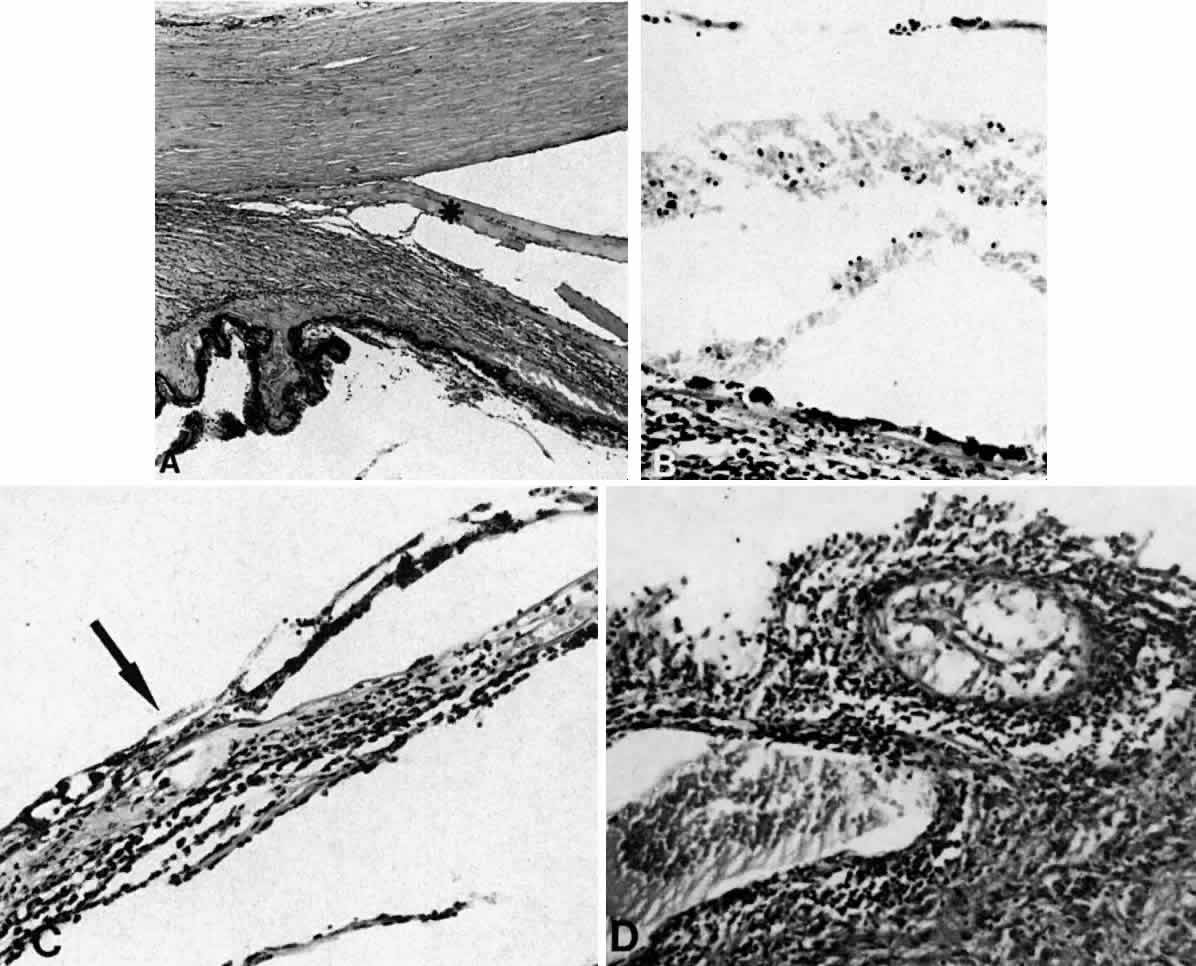

Fig. 13. A. A ciliochoroidal effusion (asterisk) associated with Toxoplasma retinochoroiditis (H & E, × 50). B. The retina temporally is totally necrotic with encysted T. gondii (H & E, × 25). C. An old chorioretinal scar (arrow) posterior to the area of necrotic retina (H & E, × 160). D. Intense vasculitis and perivascular lymphocytic infiltration of the central vessels in the optic nerve head (H & E, × 185).